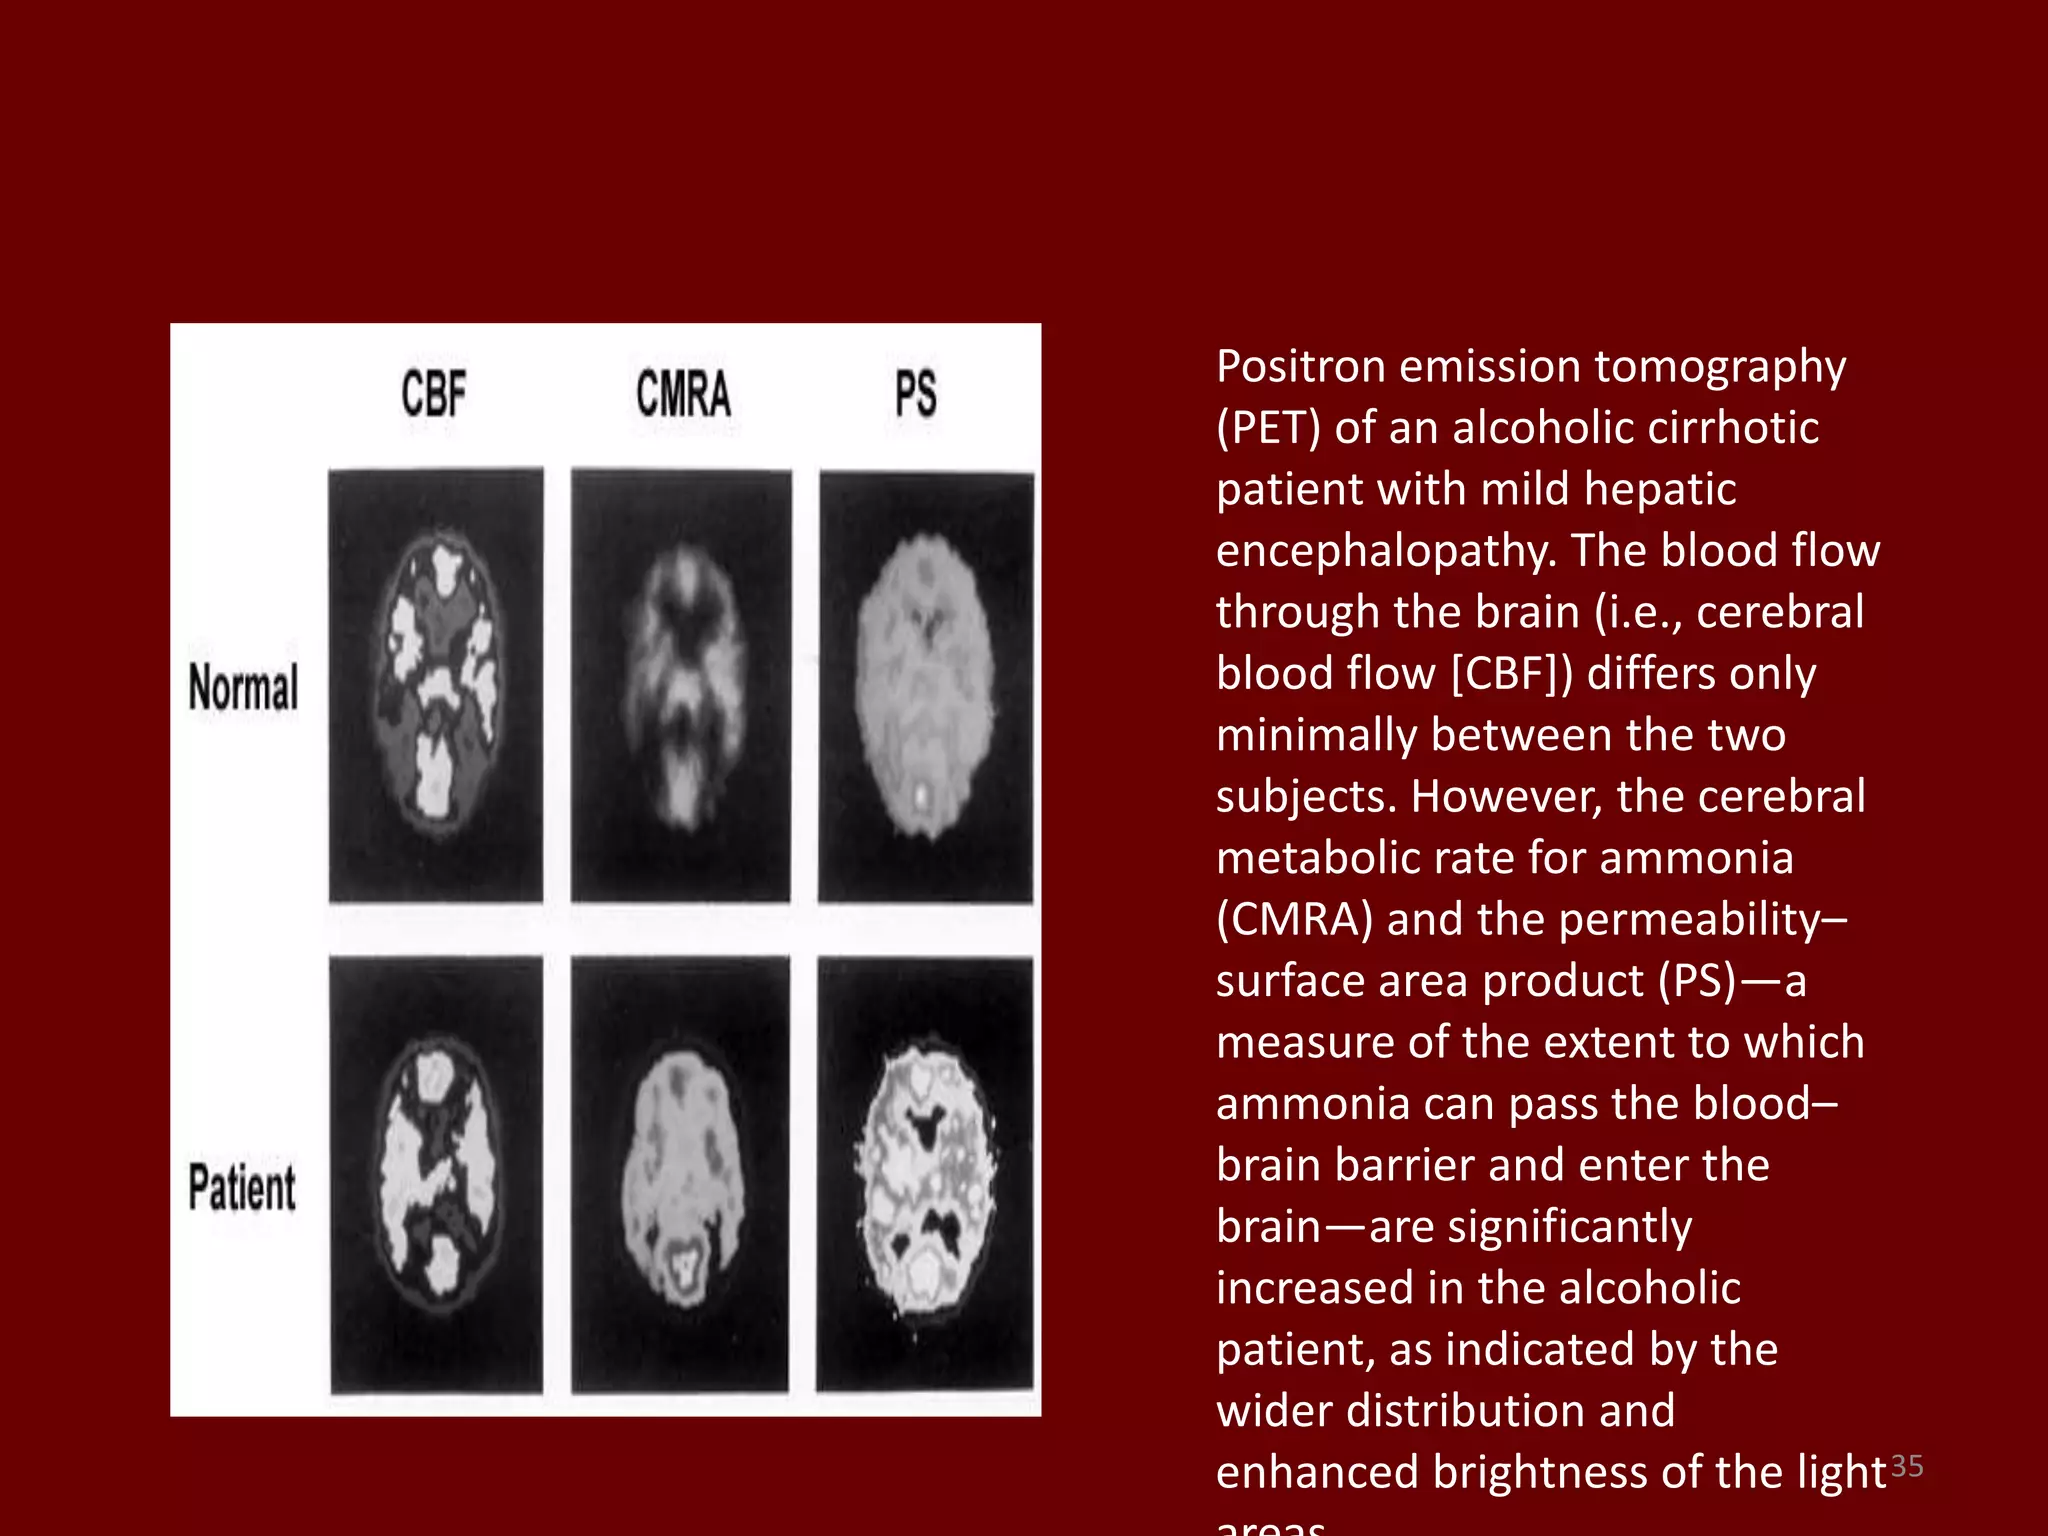

– PET has also been used in the study of the

pathophysiological mechanisms of HE.

Positron emission tomography

(PET) of an alcoholic cirrhotic

patient with mild hepatic

encephalopathy. The blood flow

through the brain (i.e., cerebral

blood flow [CBF]) differs only

minimally between the two

subjects. However, the cerebral

metabolic rate for ammonia

(CMRA) and the permeability–

surface area product (PS)—a

measure of the extent to which

ammonia can pass the blood–

brain barrier and enter the

brain—are significantly

increased in the alcoholic

patient, as indicated by the

wider distribution and

enhanced brightness of the light